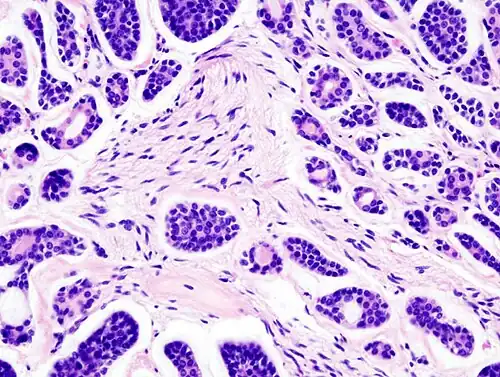

Micrograph of an adenoid cystic carcinoma of a salivary gland (right of image): Normal serous glands, typical of the parotid gland, are also seen (left of image), H&E stain.